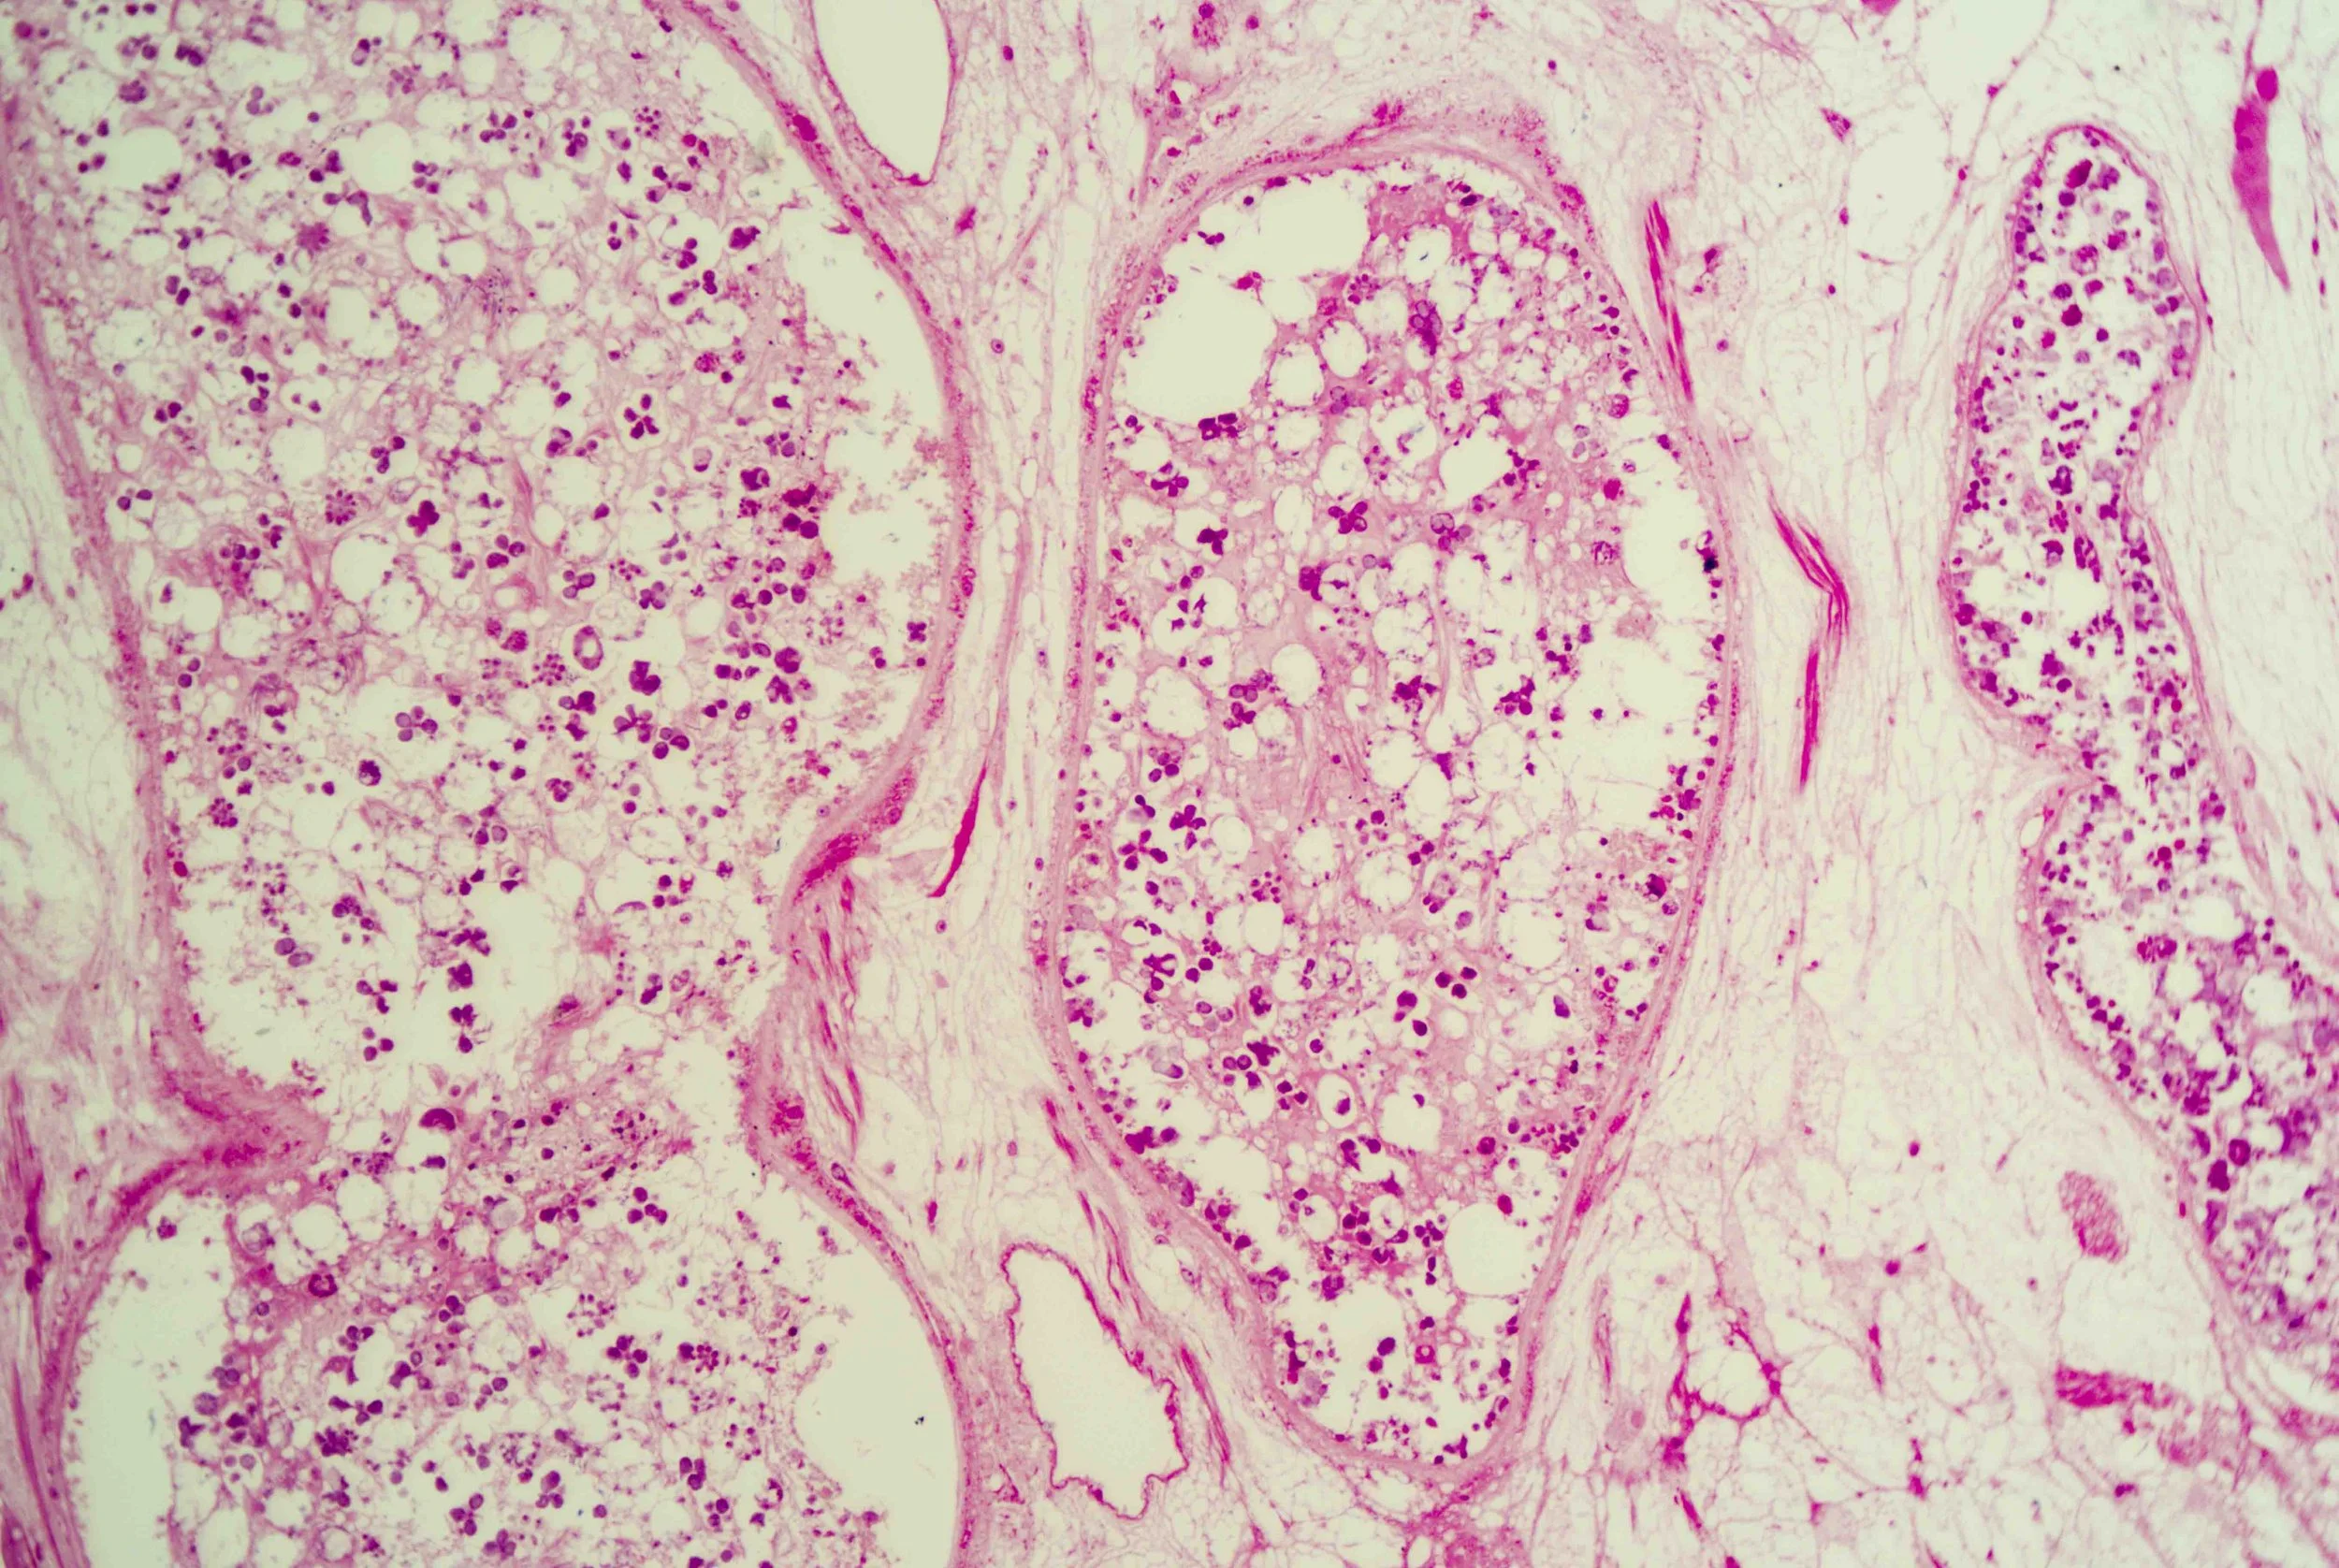

At first glance, a liver fluke is a simple, leaf‑shaped flatworm. Under magnification, however, a cross‑section reveals a labyrinth of chambers and cells, like stained‑glass windows filled with pink and purple mosaics. These sections show the parasite’s densely packed tissues, reproductive organs and digestive sacs nestled within its protective tegument.

The anterior end forms a conical “head” bearing a small yet powerful oral sucker used for feeding and adhesion. Just behind it lies a larger ventral sucker (acetabulum) that anchors the fluke to its host’s tissues.

The surface of the fluke is wrapped in a syncytial tegument—a scleroprotein‑rich skin enveloped in glycocalyx—that protects the parasite from digestive enzymes and allows nutrient absorption.

Tiny spines on this tegument become more numerous and multi‑pointed as the fluke approaches the bile ducts, helping it anchor and resist the flow of bile.

Liver flukes are hermaphrodites, carrying both male and female reproductive organs. They feed primarily on blood within the host’s liver and bile ductsen.wikipedia.org, and their branched intestine distributes nutrients throughout the body.

Yet there is an eerie beauty in their design. The intricate patterns seen in histological sections hint at the fluke’s complex adaptations—suckers, tegument, branched gut and prolific reproductive tissues—all evolved to exploit its ecological niche.